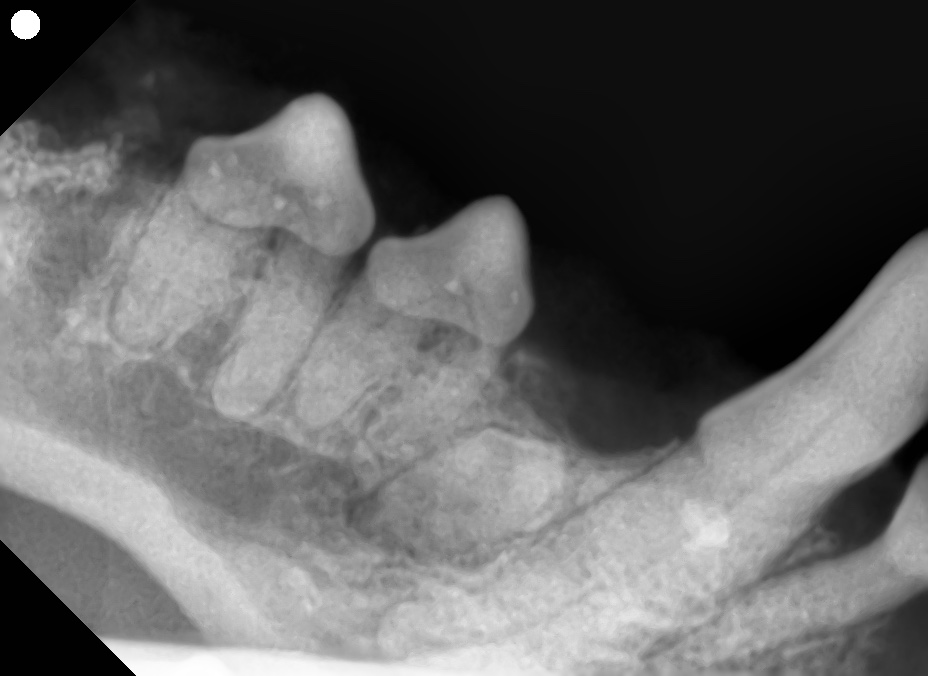

埋伏歯とは、本来萌出するはずの永久歯が、歯肉や顎の骨の中にとどまって出てこない状態を指します。

「歯が少ない=欠如歯」と思われがちですが、実際には X線検査を行うことで埋伏している歯が見つかることもあります。

外見上は「歯が生えていない」だけなので、鑑別には 歯科レントゲン撮影 が必須です。

埋伏歯の臨床上の問題は、周囲組織に発生する 歯原性嚢胞 です。

- 報告によって差はありますが、埋伏歯に関連して約30〜50%で嚢胞形成が確認されたとされています。

- 嚢胞は無症状に進行し、気づいたときには顎骨の広範な吸収や病的骨折につながるケースもあります。